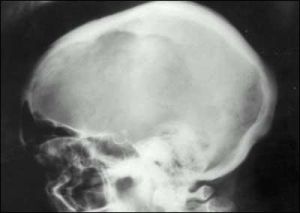

為雙顳部顱骨增大,前額隆起,頭皮靜脈曲張,一側或雙側神經性耳聾或耳硬化症,眼底有血管樣紋,軀幹矮而駝背,形似猿猴。蹣跚步態,股或小腿前外側彎且有骨膜壓痛和溫度升高。聽覺喪失,脊髓狹窄症,不全麻痹或截癱均為神經受壓的表現。因Paget骨病是代謝活躍而且血管嚴重受累的病變,故可發生高排性心力衰竭。彎曲的長骨與鄰近關節的骨關節炎可發展為畸形。可發生病理性骨折。約1%的病人發生肉瘤變性,此時疼痛越來越劇烈。

X線檢查有助於診斷受累及病灶區。骨端受累、溶骨區界限銳利、楔形透光區、廣泛性硬化、骨體積增大、骨小粱變粗等有助於與其他疾病鑑別。廣泛的骨密度增加應與骨轉移癌(尤其是前列腺癌骨轉移)、骨髓纖維化、腎性骨病、氟骨症、纖維異常增殖症和結節性硬化症鑑別。變形性骨炎累及顱骨時可出現顱骨肥大,應與額骨內板肥厚症、纖維異常增殖症、貧血和骨轉移癌等鑑別。本病盆骨硬化呈非對稱性或單側分布、受累骨增大、骨小粱增粗。累及脊椎時,病變椎體呈框架征,四周濃密。血管瘤所致者表現為縱向骨小粱增粗,腎性骨病除有腎臟本身的疾病外。特徵為橄欖球衣狀脊椎。

X線的表現較複雜可歸納為下列數點:①骨質破壞骨小梁粗糙稀疏伴局限性骨質疏鬆晚期的骨皮質與髓質腔界限不清,結構模糊如網狀;②骨幹增粗,膨大,彎曲變形,呈腰刀狀;③顱骨局限性骨質疏鬆伴棉絮狀增生,內外板界限消失,顱縫模糊,頭顱增大;④椎體呈柵欄狀和方框狀改變;⑤長骨溶骨性病灶有時呈V形;⑥骨盆連緣和弓狀線增厚,出現邊緣征;⑦髖關節間隙變窄,骨質增生短骨增粗;⑧病變區病理性骨折。